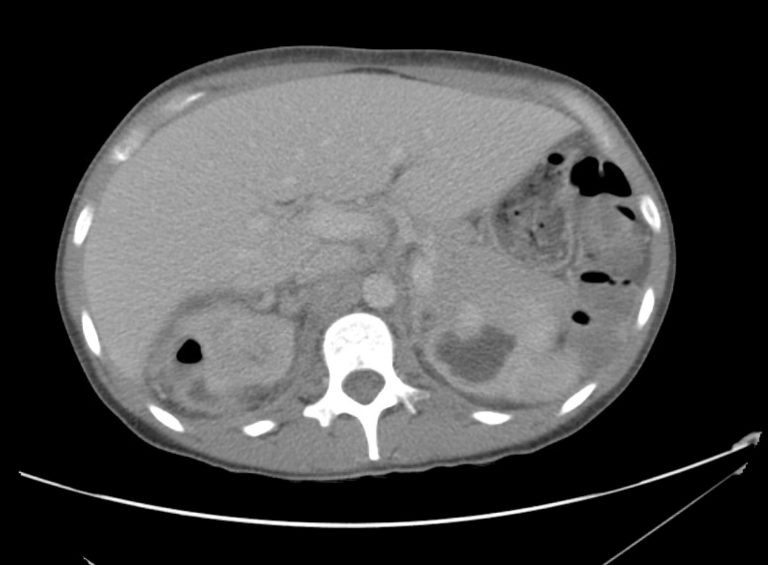

From ultimate-radiology.blogspot.com

Ultimate Radiology CASE OF BILATERAL PYELONEPHRITIS Pyelo Nephr Itis A urinary tract infection is described by location: Young children with a uti need medical attention. Learn about symptoms and treatment here. management of pyelonephritis in adults. A kidney infection (pyelonephritis) can be unpleasant, but it will usually improve if treated promptly. If not treated properly, an infection can cause lasting damage to the kidneys. Pyelonephritis is generally a. Pyelo Nephr Itis.